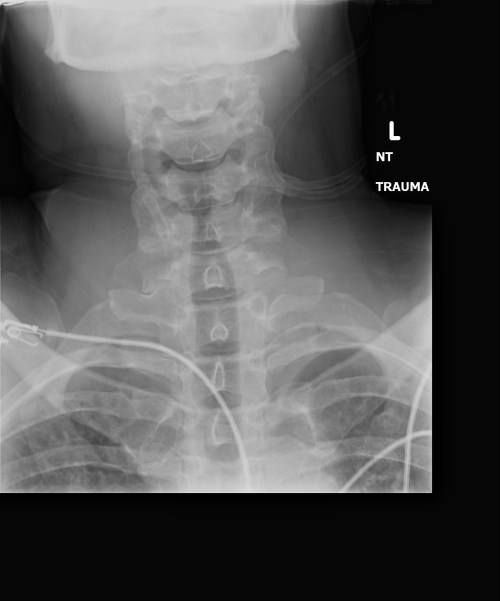

Stomach-Churning Rating: 4/10; semi-gruesome x-rays of me and hippo bits at the end, but just bones really.

X-ray of my right shoulder from frontal view, unlabelled

Labelled x-ray